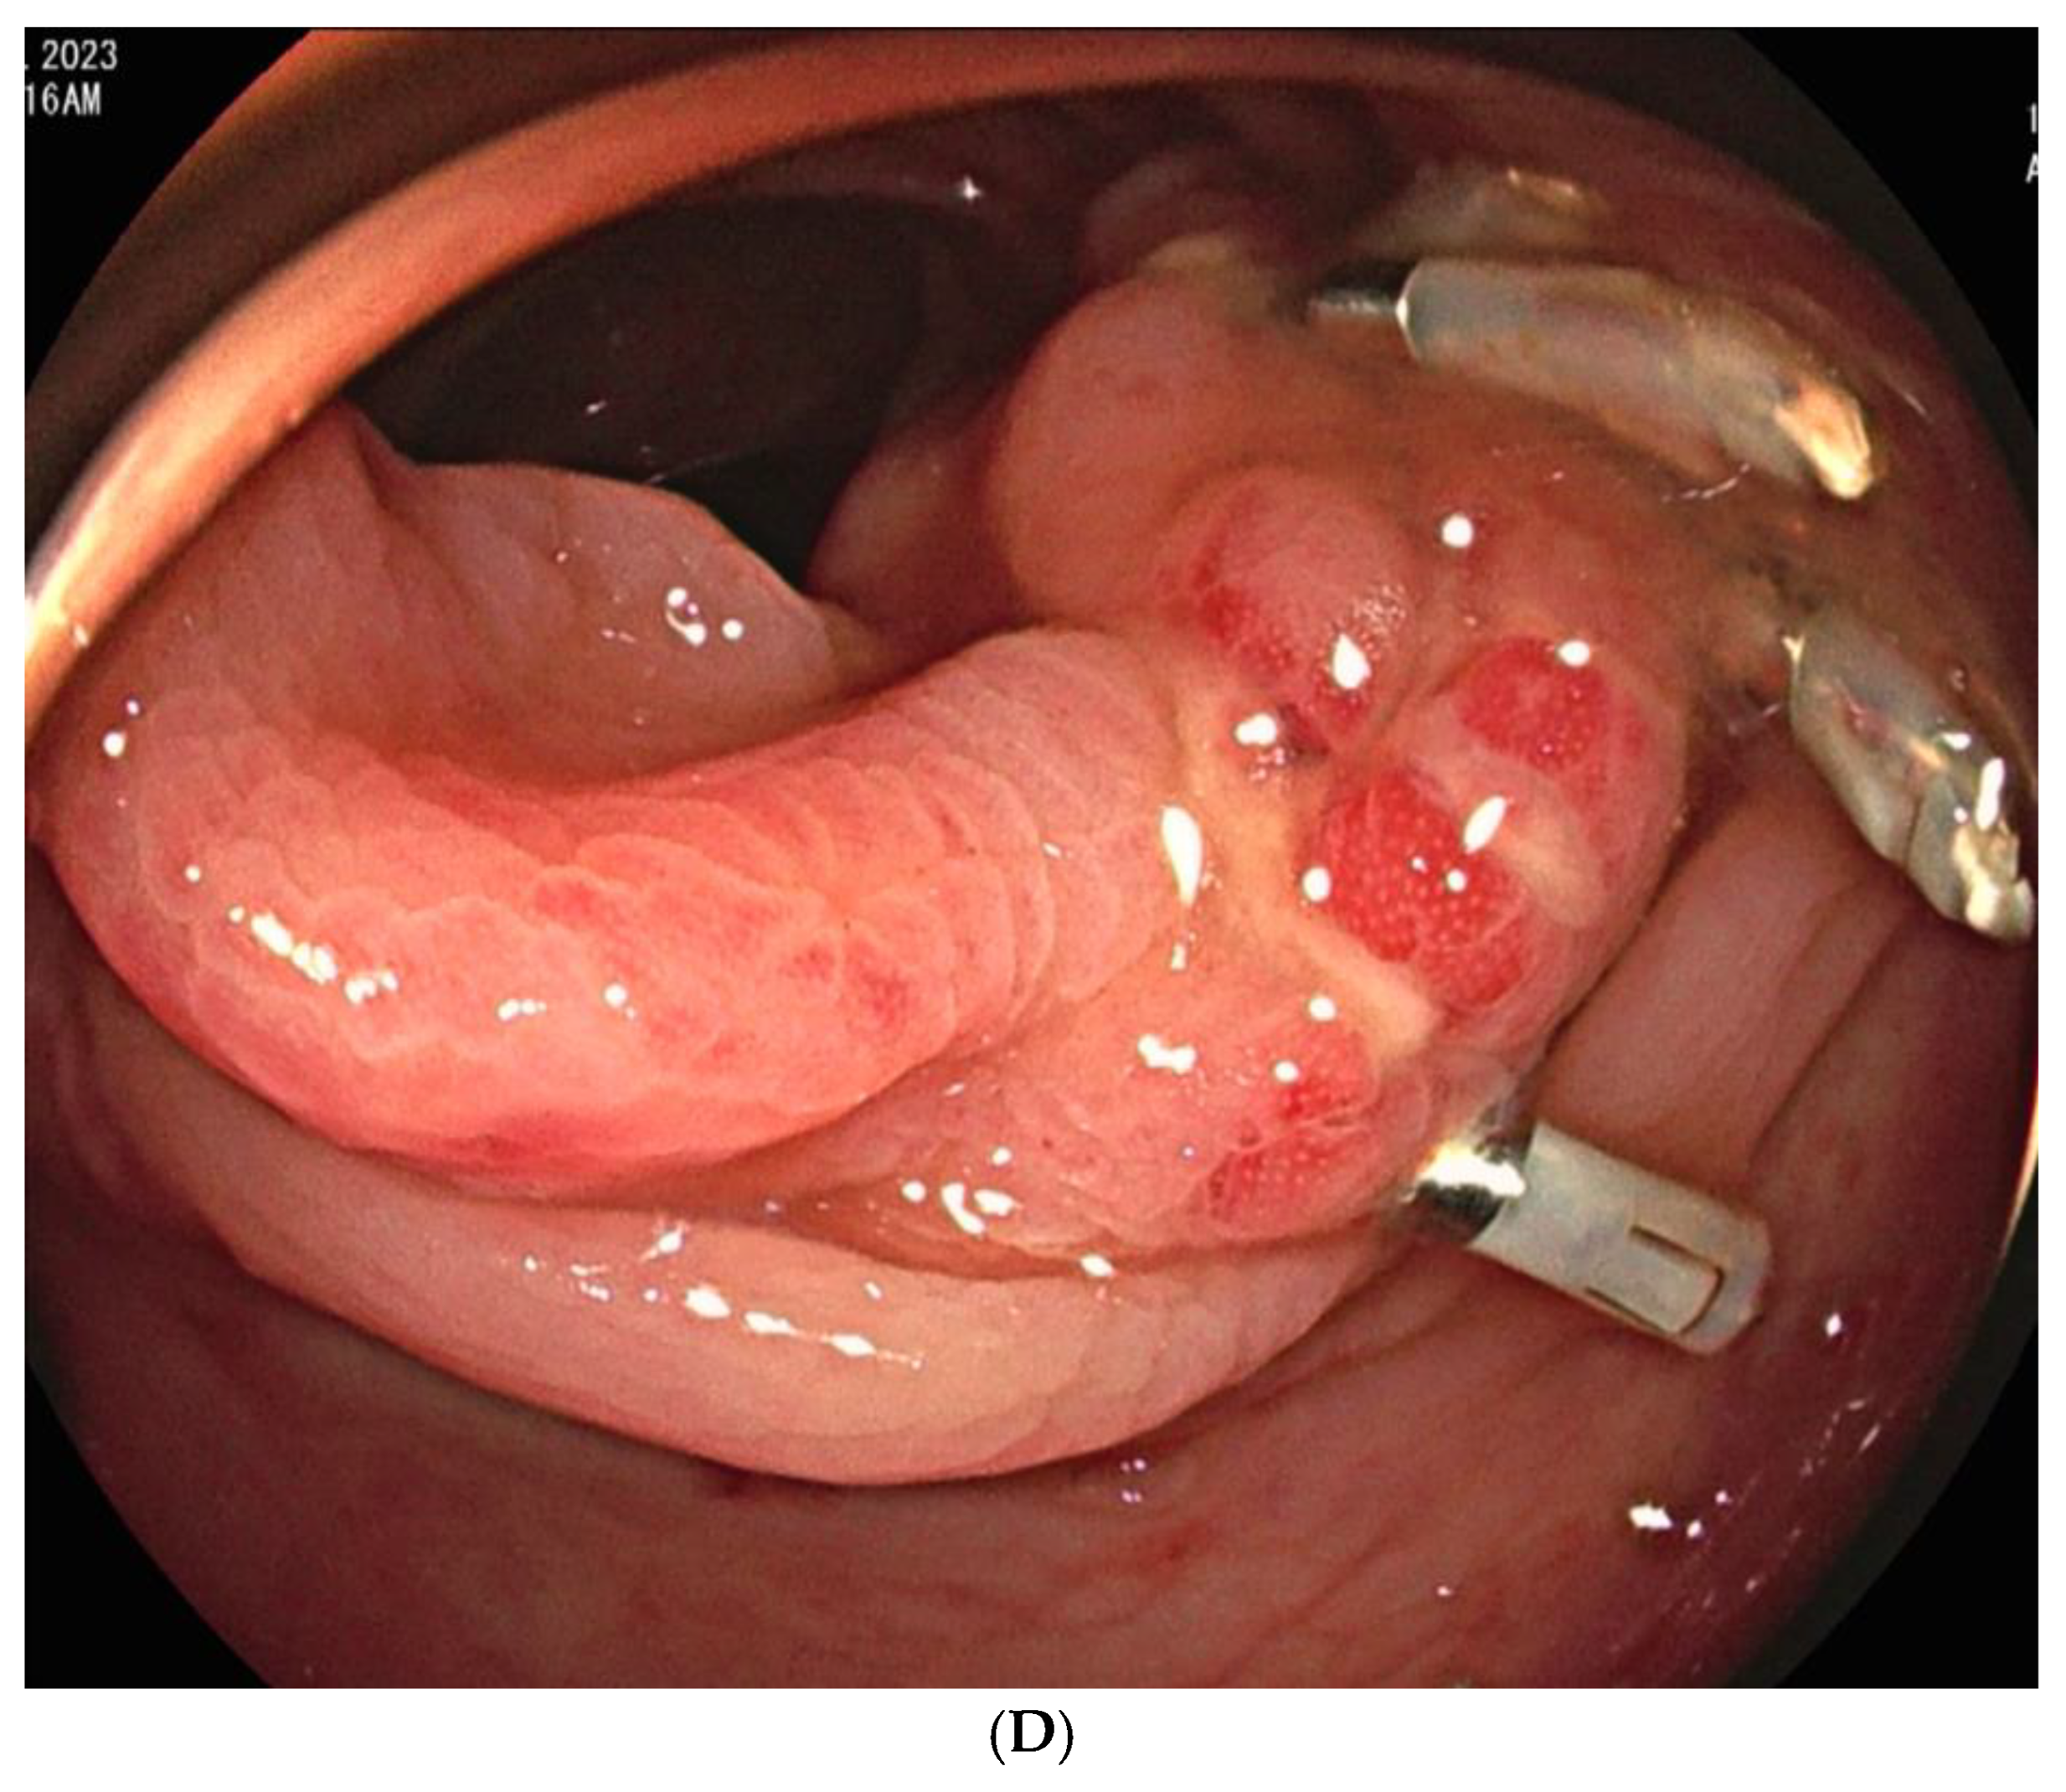

Figure 3. A 59-year-old man with colonic diverticula presented with hematochezia. (A) Contrast-enhanced axial CT image shows colonic diverticula with luminal contrast extravasation (arrow) at the hepatic flexure. Sigmoidoscopy performed one day after the CT scan reveals a diverticulum with bleeding (inset). Endoscopic hemoclipping was performed (not shown). (B) Superior mesenteric arteriography demonstrates focal hypervascularity (arrows) around the endoclipping site, without evidence of contrast extravasation. As superselection was not possible, the arterial branches leading to the endoclipping site were embolized using quick-soluble gelatin sponge particles (150–350 µm). (C) Post-embolization arteriography shows marked reduction in the previously observed hypervascularity around the endoclipping site. (D) Sigmoidoscopy performed two days after embolization reveals several ulcers and erythematous changes around the hemoclipping site, consistent with ischemic colitis. Associated abdominal pain resolved within three days. No further bleeding occurred during the 6-month follow-up.